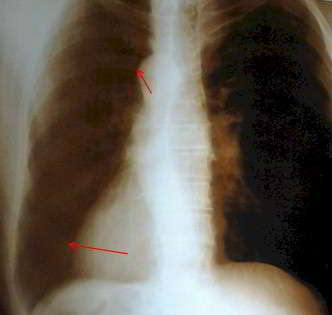

Radiografía tórax que muestra corazón en situación anormal.

Como se puede apreciar el Situs inversus es una rara entidad por lo que es interesante presentar un caso diagnosticado y hacer énfasis en un adecuado examen físico y luego la comprobación con estudios imagenológicos, para la corroboración sin la necesidad de trasladar al paciente a un centro hospitalario para realizar estudios complementarios, especialmente por las condiciones económicas del paciente quién no accedió a realizarse más exámenes, pero con los pocos recursos que se contaban en la mencionada casa de salud se pudo concluir que se el paciente presento una dextrocardia también conocida como situs solitus con dextrocardia.